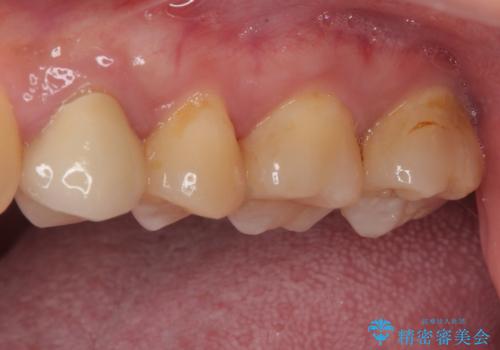

- 奥歯に物が挟まるとのことで来院された患者様です。

レントゲン写真より、奥歯2本に大きなむし歯があることが分かりました。

手前の歯はセラミックインレーで、奥の歯はオールセラミッククラウンにて治療を行うこととしました。

むし歯の範囲は大きかったですが、事前の症状もなく、処置後も一切の痛みなく快適に過ごすことができています。